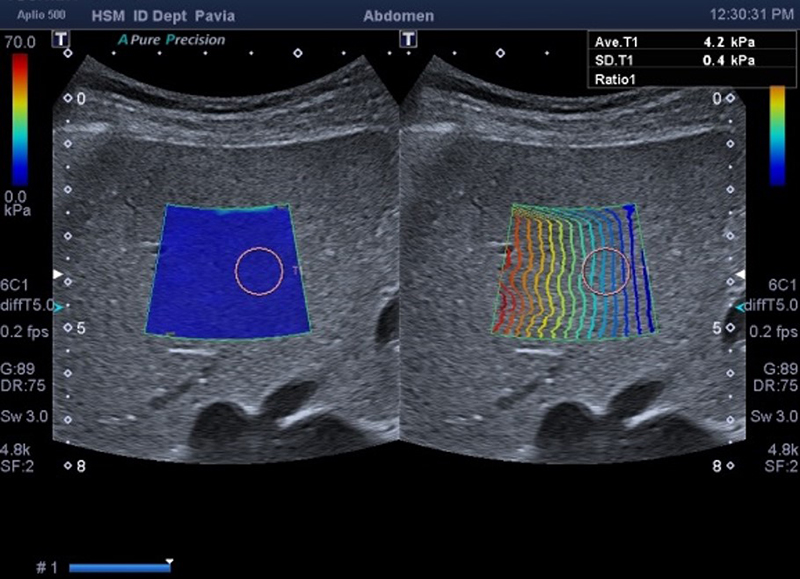

Саме застосування УЗД-апаратів від CANON MEDICAL повністю змінило стандарти діагностики фіброзу печінки — еластографія використовує ультразвук в реальному часі для оцінки еластичності тканин і є швидким, простим, відтворюваним і надійним методом неінвазивної оцінки фіброзу печінки.

Тобто еластографія – сучасний неінвазивний метод ультразвукової діагностики, який дозволяє оцінити ступінь фіброзу печінки при хронічних її захворюваннях.

Для правильного трактування отриманих результатів нагадуємо вам, шановні колеги, шкалу фіброзу, адаптовану та рекомендовану для використання на приладах CANON MEDICAL.

Ultrasound Shearwave for Staging Liver Fibrosis: Preliminary Results of a Prospective Multicenter European Study

Stage Fibrosis Stage Speed (m/s) Elasticity (kPa)

F0-F1 Non significant < 1,54 < 7.1

≥ F2 Significant 1,54 - 1,78 7,1 – 9,5

≥ F3 Advanced 1,78 – 1,87 9,5 – 10.5

F4 Cirrhosis > 1,87 > 10.5